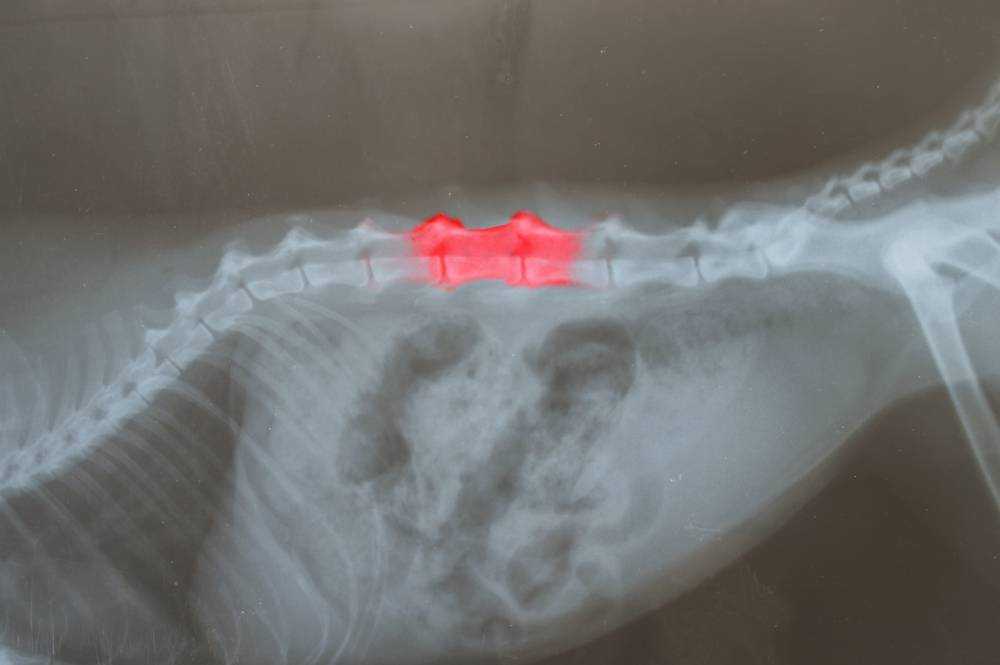

К признакам болезни межпозвонковых дисков Хансен тип 1 при рентгенографии относятся сужение межпозвонкового пространства, межпозвонковых отверстий и пространства между суставными отростками. Если ядро выпавшего диска подверглось обызвествлению, то иногда его можно заметить в позвоночном канале, но это бывает крайне редко. При заболевании межпозвонковых дисков Хансен тип 2 на рентгене можно наблюдать другую картину. При хронических проблемах типичными признаками, помимо сужения межпозвонкового пространства и отверстий, являются склероз суставных пластинок позвонков, образование остеофитов, спондилез и прочее. Особенно выражено это при люмбо-сокральном стенозе («синдром конского хвоста»).

Для выявления очага компрессии рентгенография недостоверна. В таком случае используют миелографию, МРТ или КТ.